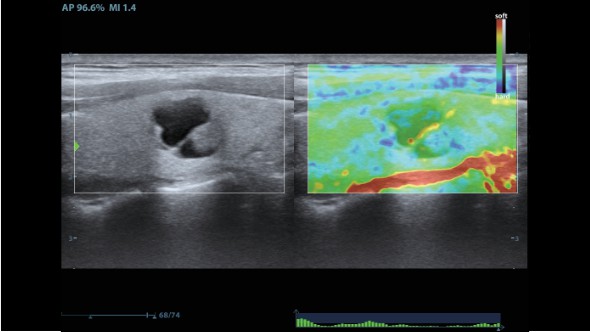

Клинические изображения